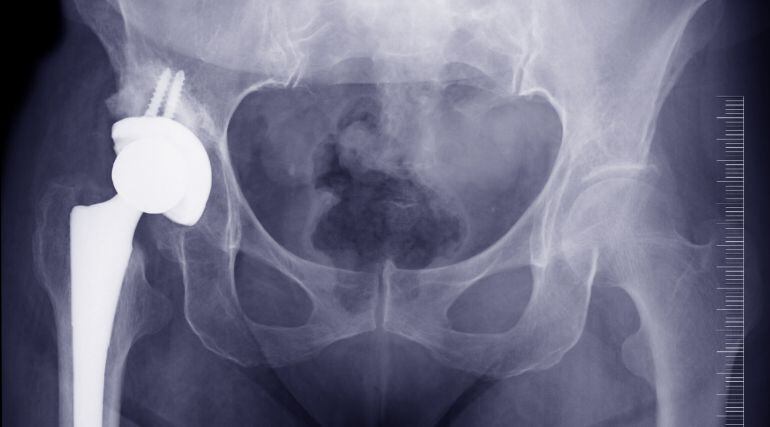

El Col·legi calla de moment sobre la decisió del jutge del cas INNOVA, que acusa a 50 cirurgians de 30 hospitals catalans de cobrar comissions a canvi de col·locar les pròtesis de maluc defectuoses de l'empresa Traiber